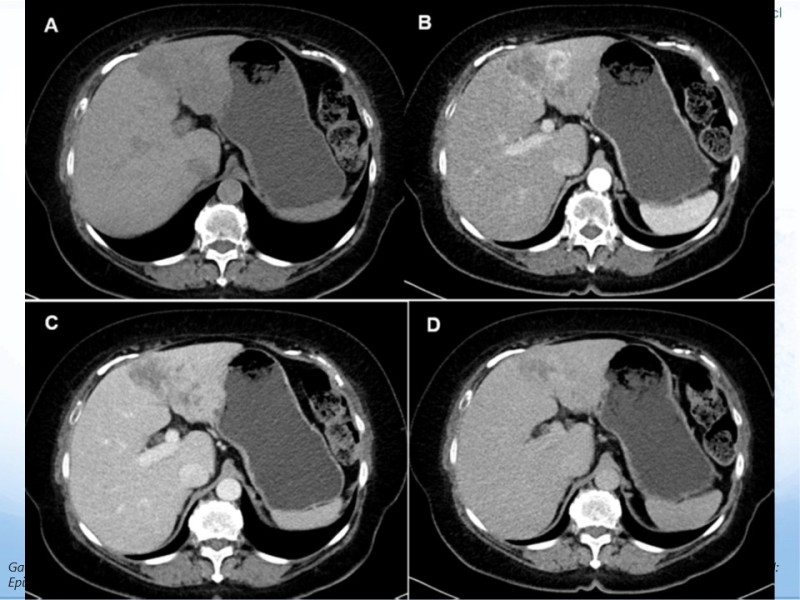

Colangiocarcinoma

Hepatobiliopancreático

| Autor: Dr. Felipe Villalobos Hermosilla